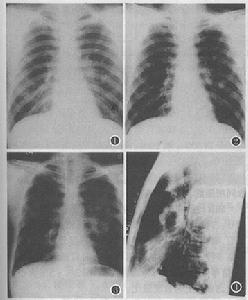

胸部X線檢查可能正常,也可能有瀰漫性間質纖維化。常出現雙側性斑塊或結節樣浸潤,支氣管肺紋理增粗,或呈小的腺泡樣改變,提示有肺水腫。肺門淋巴結腫大和胸腔積液罕見。CT特別是高分辨CT對判斷病變類型和範圍有較高價值,但CT表現無一定規律性。